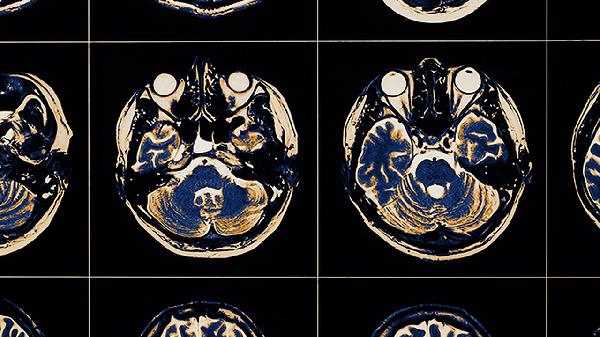

患者会出现时间、地点、人物定向力完全丧失,可能在家中迷路,将白天误认为黑夜。这与大脑顶叶和额叶功能受损相关。家属需保持家居环境固定不变,避免频繁更换物品位置。医生可能通过脑电图和头部MRI评估病变范围。